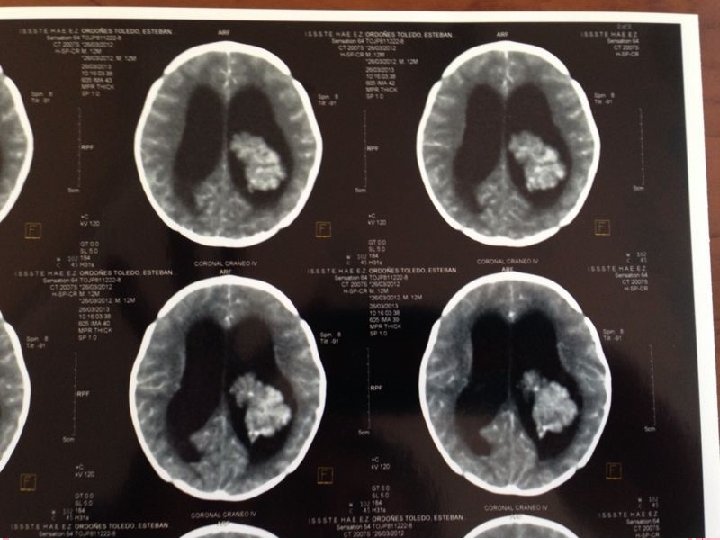

ANGIOGRAFÍA CEREBRAL Antes era fundamental el estudio del síndrome hidrocefálico, actualmente han quedado relegadas. Solo se utilizan para estudio de malformaciones vasculares que pudieran desencadenar hidrocefalia TOMOGRAFÍA CEREBRAL MÉTODO DE ELECCIÓN Tamaño de Cavidades ventriculares Causa Etiológica Villarejo Francisco. Martínez Lage Juan F. “NEUROCIRUGÍA PEDIÁTRICA”. Ediciones Ergón. Madrid España 2001 Neumoencefalografía Ventriculografía Cisternografía isotópica

Criterios para TAC Presencia de dilatación ventricular Hipodensidad en polos occipitales y frontales periventriculares Borramiento de los surcos cerebrales INDICE DE EVANS : igual o superior a 0. 30 debe considerarse patológico Cuernos temporales con diámetro mayor a 2 mm Lopez Ojeda Pablo, DIAGNOSTICO Y TRATAMIENTO DE LA HIDROCEFALIA CRONICA EN EL ADULTO, Barcelona hospital universitario 2009

Criterios para TAC FH/ID >0. 5 Abombamiento de los cuernos frontales y ventrículos laterales

Lopez Ojeda Pablo, DIAGNOSTICO Y TRATAMIENTO DE LA HIDROCEFALIA CRONICA EN EL ADULTO, Barcelona hospital universitario 2009